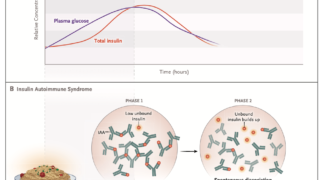

内分泌学的所見では、GH・PRLが検出下限以下で、TSH・IGF-1・fT4が低値を示す。

負荷試験でこれらのホルモンの反応が悪い。

下垂体MRIでは明らかな異常が認められないため、原因不明の中枢性甲状腺機能低下症と診断されることが多い。しかし、造影MRIを行うと一部の患者では不均一な増強を伴うわずかに萎縮した下垂体前葉が認められる。